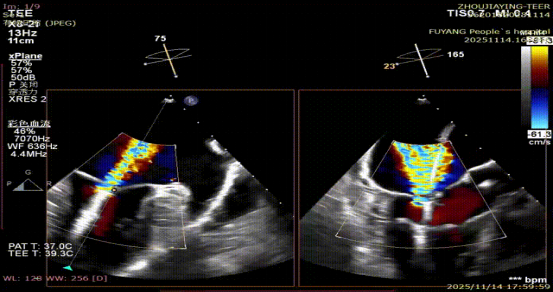

手术当日,在全身麻醉及TEE全程导航下,陈玺全副主任团队凭借丰富的临床经验与精湛操作技巧,顺利完成房间隔穿刺、瓣叶精准定位等关键步骤。针对患者二尖瓣A2/P2 区域反流靶点,团队精准夹合瓣叶,经X-plane技术与三维超声反复确认夹持质量后,成功释放一枚MitraClip XTR夹子。术后即时评估显示,患者二尖瓣反流由术前3 +重度降至轻度,平均跨瓣压仅3mmHg,手术达到预期效果,全程无并发症发生。

术后PV前向改善